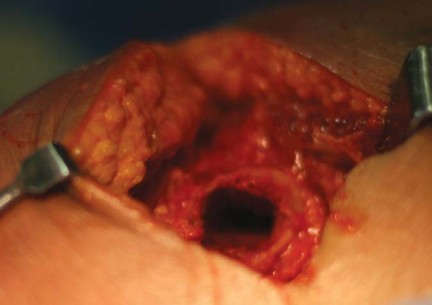

تصميم مفصل METHA

يُعد METHA جذعًا معياريًا، يُثبت في الميتافيزال، وغير إسمنتي. يتميز بتصميم مستوحى من مفصل Mayo الناجح، ولكنه يتفوق عليه في عدة جوانب:

- شكل شبه منحرف واسع: يوفر ثباتًا أوليًا ممتازًا مع الحفاظ على العظم الإسفنجي.

- مادة الصنع والطلاء: يتكون من جذع مخروطي مزدوج من التيتانيوم، مغطى بالكامل بطلاء التيتانيوم النقي المسامي الدقيق (بلازمابور) مع طبقة رقيقة من فوسفات الكالسيوم ثنائي الهيدرات. هذا الطلاء يعزز التوصيل العظمي ويؤدي إلى اندماج عظمي مبكر، مما يوفر ثباتًا ثانويًا.

- الطرف البعيد غير المطلي: يعمل كدليل للزرعة على طول القشرة الظهرية الجانبية، مما يعزز الثبات الأولي العالي. لا يشارك طرف الجذع بشكل كبير في نقل الحمل، بل يعزز الثبات المحوري.

- وحدات الرأس والعنق المعيارية: تتوفر تسعة محولات للعنق مصنوعة من الكوبالت والكروم، بزوايا عنق الفخذ 130، 135، 140 درجة، وزوايا دوران 0، 7.5 درجة أمامية، و7.5 درجة خلفية لكل زاوية. تتوفر الجذوع بسبعة أحجام من 0 إلى 6. تسمح هذه المحولات المعيارية بتحسين ميكانيكا مفصل الفخذ لكل مريض على حدة دون إطالة الطرف.

التقنية الجراحية لزراعة METHA

تتطلب جراحة METHA دقة متناهية وخبرة عالية لضمان أفضل النتائج. يُعد الأستاذ الدكتور محمد هطيف في صنعاء خبيرًا في تطبيق هذه التقنية المتطورة.

النهج الجراحي

يمكن استخدام أي نهج جراحي لزرع METHA. إن قطع عنق الفخذ القريب ونقطة الدخول الإنسية تجعله مناسبًا للنهج الأمامي، الأمامي الجانبي، والخلفي طفيف التوغل. يفضل الأستاذ الدكتور محمد هطيف إجراء الجراحة من خلال شق مناسب الحجم ونهج خلفي، مع وضع المريض في وضعية جانبية.